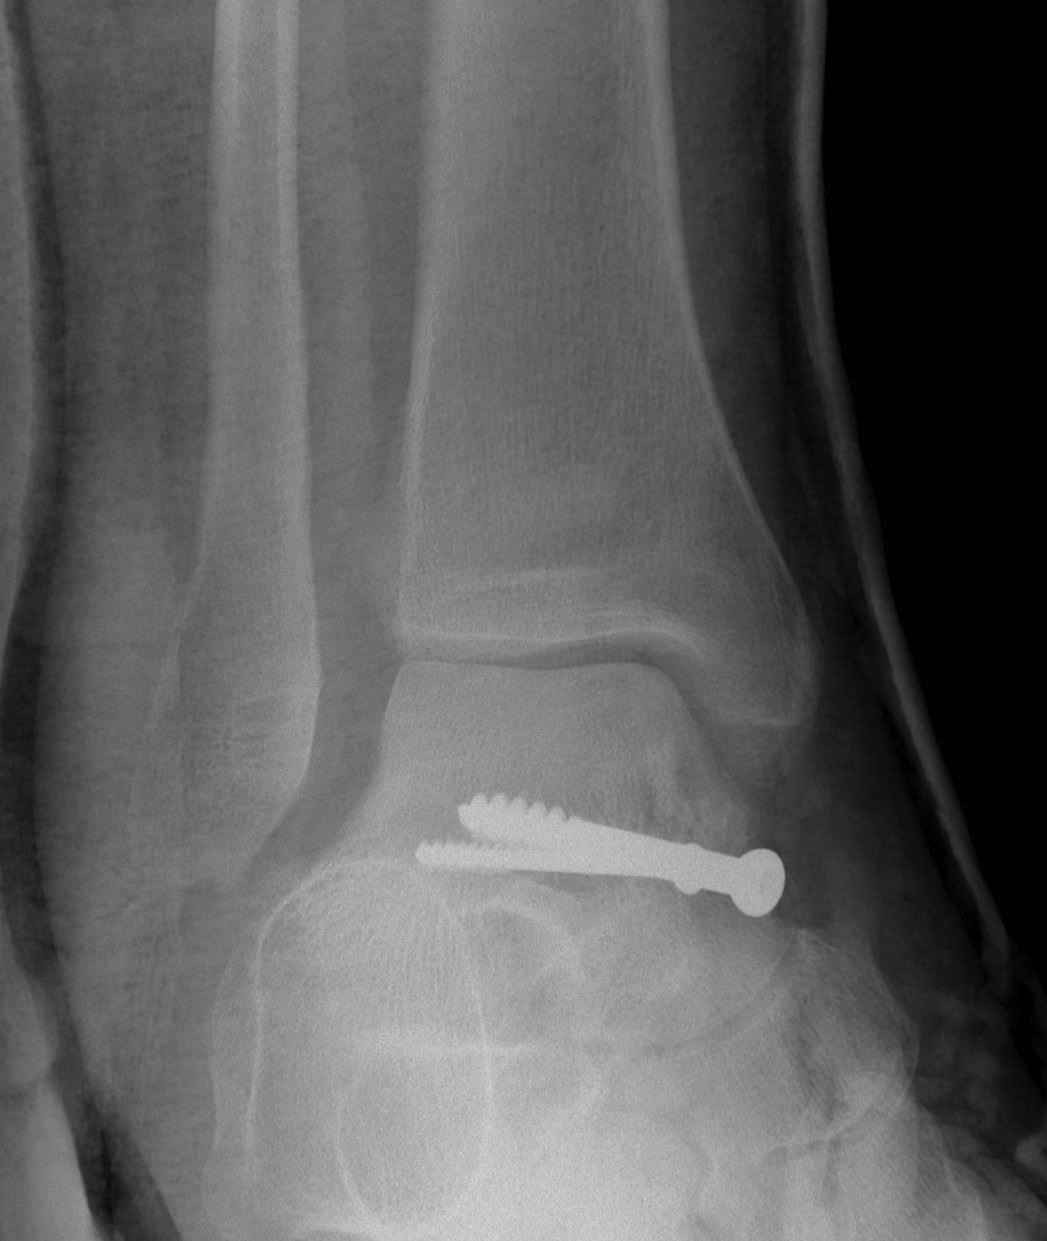

trimallTrimallTrimallTrimall

ankeankleankleankle